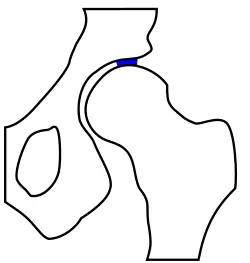

unten: gesundes Hüftgelenk

Für die Diagnostik einer Hüftgelenksarthrose ist normalerweise eine röntgenologische Untersuchung ausreichend. Gewöhnlich werden Röntgenaufnahmen in zwei Ebenen durchgeführt:

Das Röntgenbild kann auch Auskunft über präarthrotische Deformitäten, beispielsweise bei einer Hüftdysplasie (vgl. Abb.) als Ursache der Coxarthrose geben.[18] Hier ist der Hüftkopf nicht ausreichend überdacht und steht deswegen dezentriert nach oben / seitlich heraus. Dadurch resultiert eine Verkürzung der Beinlänge. Im Laufe der Zeit kommt es zu einer massiven „Entrundung“ des Hüftkopfes, der Gelenkspalt ist fast ganz aufgehoben, das Hüftgelenk wird steif.